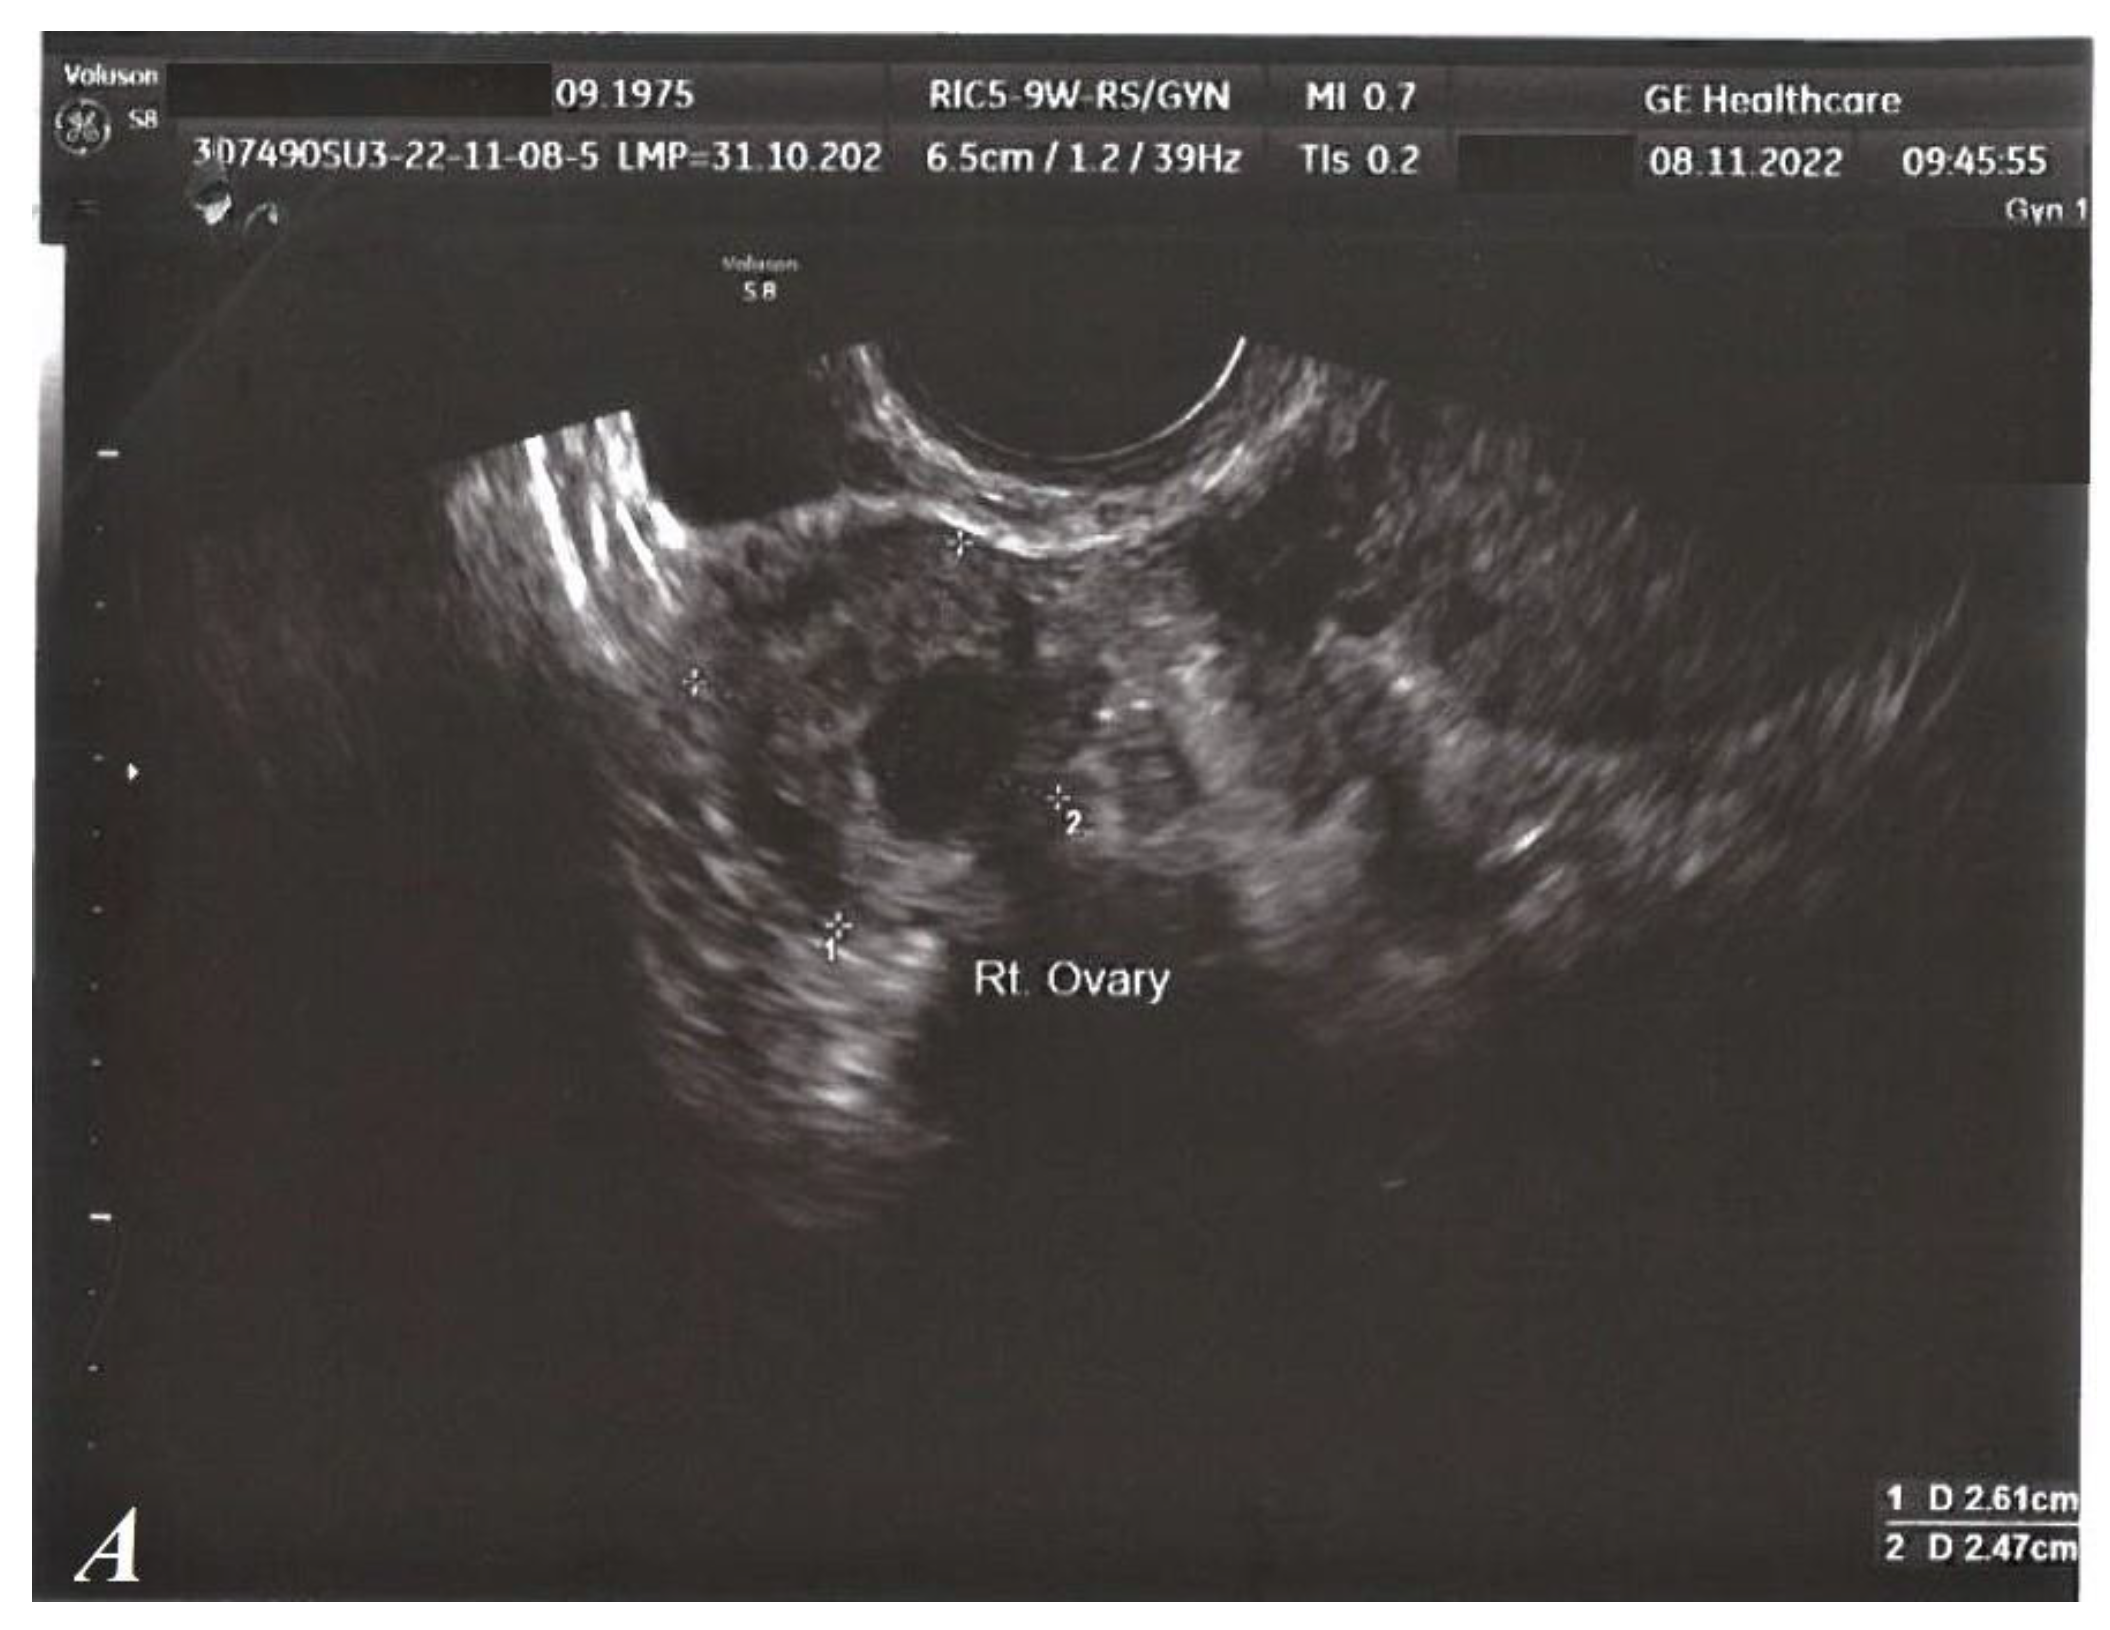

Regarding local GYN examination, as well as standard transvaginal ultrasound (TVUS), no clinical pathological signs were detected. (Figure 2).

Figure 2.

TVUS, normal aspect. Right ovary (A). Left ovary (B). Uterus (C).